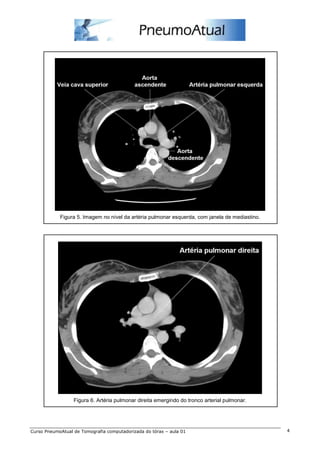

Figura 5. Imagem no nível da artéria pulmonar esquerda, com janela de mediastino.

Figura 6. Artéria pulmonar direita emergindo do tronco arterial pulmonar.